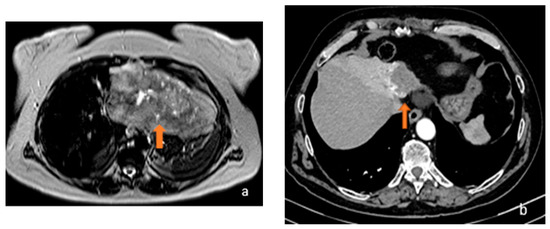

3.1. FLL Feature Characteristic

5.1. FLL Feature Characteristic